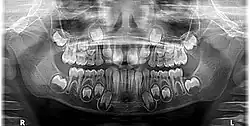

Radiographic appearance

On radiographs, enamel appears as the most radiopaque (white) structure due to its high mineral content.[19] Dentine and cementum are less radiopaque and are usually indistinguishable from each other.[19] The pulp chamber and root canals are radiolucent (dark), centrally located within the tooth structure. The periodontal ligament appears as a thin, radiolucent line between the root and the lamina dura.[19]